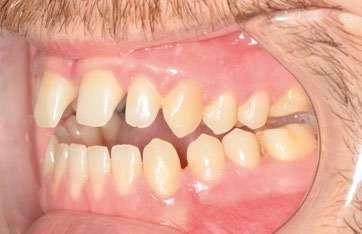

Tras colocar la anestesia palatina infiltrativa, el disyuntor osteo-soportado con tornillo hexagonal, se fijó de forma segura mediante los mini-tornillos utilizando un contra-ángulo de baja velocidad. Ese mismo día, se inició la expansión con pauta de 1 vuelta al día (0,16 mm por vuelta). Tras 43 días, se apreció la apertura de diastema inter-incisal y se continuó dando vueltas durante 18 días más hasta conseguir la corrección de la mordida cruzada posterior (Ilustración 5).

Ilustración 5. Fotografías intraorales tras la disyunción con MARPE.